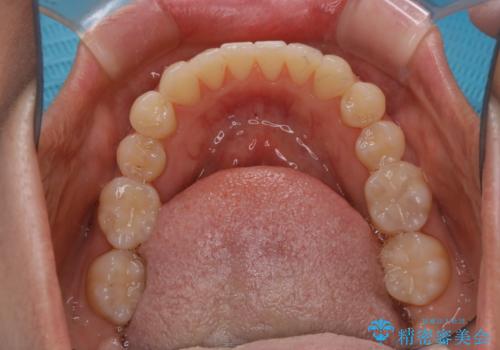

矯正治療とセラミック治療が終了後のPMTC

- 矯正治療とセラミック治療の総合治療が終了したため、クリーニングをしっかりとしてからメンテナンスに入りたいとのことでした。PMTC30分コースを行いました。

矯正治療が終わり、せっかくきれいになった歯並びも、虫歯・歯周病などになってしまっては元も子もありません。

矯正治療やセラミックなどによる被せ物の治療終了のタイミングではクリーニングを行い、汚れや着色の除去、歯と歯の間・歯と歯肉との境目などのケアをしっかりすることをおすすめしています。

ご自身での歯ブラシ・セルフケアを行うと同時に、定期的なクリーニング(PMTC)を行うことで、いつまでも健康な歯を保つことができます。